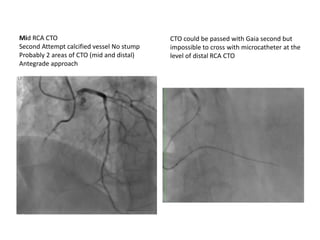

CTO could be passed with Gaia second but

impossible to cross with microcatheter at the

level of distal RCA CTO

Mid RCA CTO

Second Attempt calcified vessel No stump

Probably 2 areas of CTO (mid and distal)

Antegrade approach